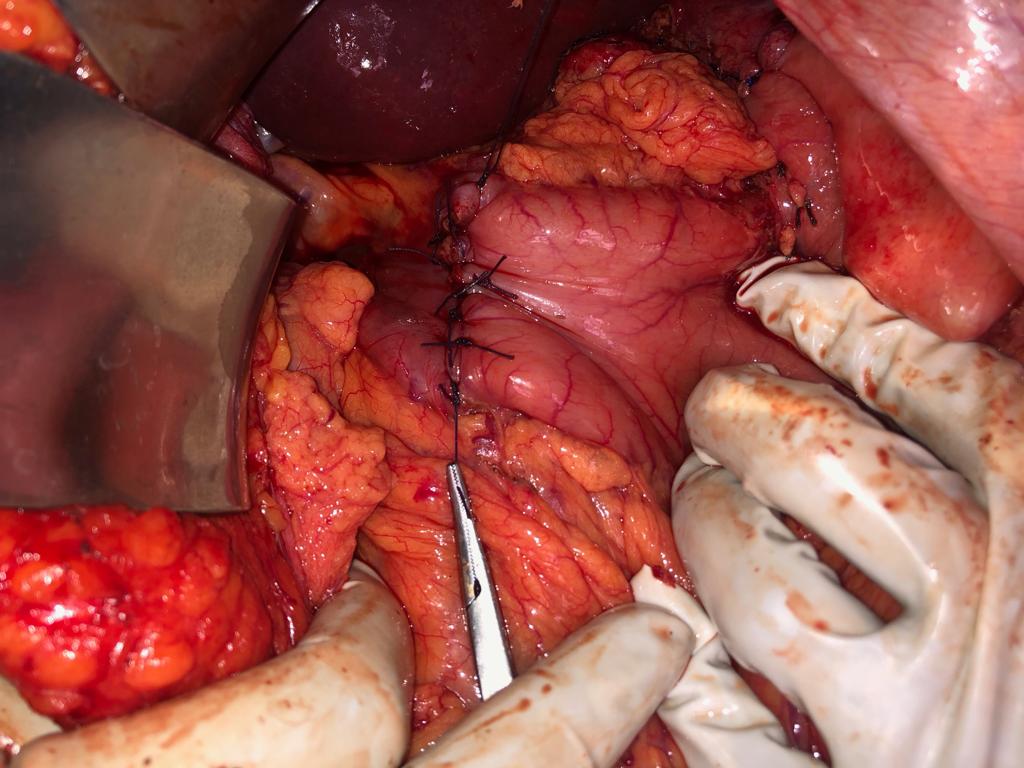

Child’s A CLD with HUGE gastric varices uncontrolled by Endoscopic glue and attempted EUS coiling. One salvage option would be TIPSS with balloon vascular occlusion but due to logistics we went for modified sugiura procedure. Splenectomy + Gastro esophageal devascularisation with anterior Gastrotomy and overseeing of gastric varices with pyloroplasty. Images show 1 CECT showing large gastric fundal varices. 2,3,4 Gastro Esophageal devasc 5, 6 Large fundal varices before and after oversewing. 7. Anterior gastrotomy 8. Pyloroplasty. Postoperative recovery was uneventful.